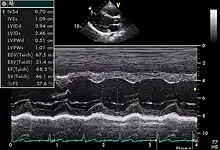

An abnormal echocardiogram: Image shows a midmuscular ventricular septal defect. The trace in the lower left shows the cardiac cycle and the red mark the time in the cardiac cycle when the image was captured. Colors are used to represent the velocity and direction of blood flow.

Echocardiogram in the parasternal long-axis view, showing a measurement of the heart's left ventricle